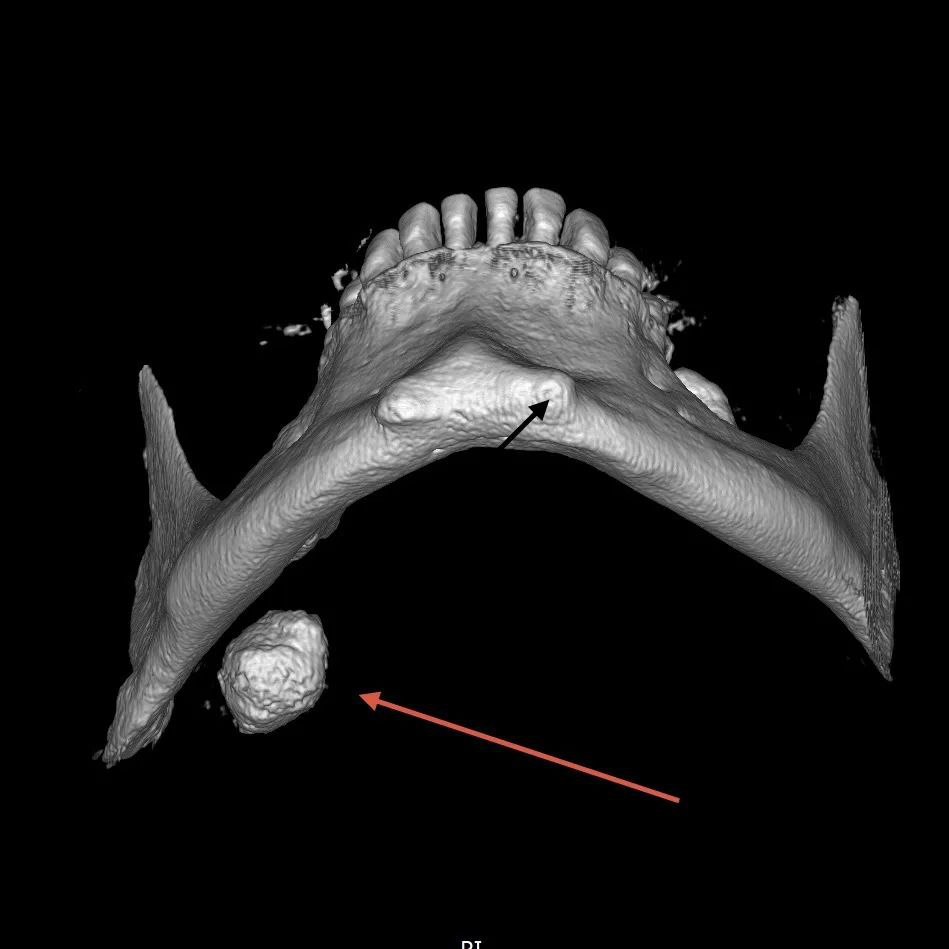

Слюнной камень растил приморец 17 лет.

Врачи Краевой больницы №2 во Владивостоке удалили из слюнной железы мужчины камень диаметром более 2 сантиметров. Он болел слюнно-каменной болезнью 17 лет, но к врачам обратился, когда камень уже стал "сказываться на качестве жизни".

Фото: Telegram-канал ККБ №2.